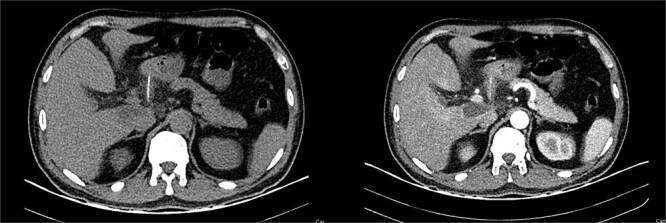

鱼骨穿孔致胃进入小网膜囊及胰腺并形成脓肿,这可不是件小事。

Fishbone perforation of the stomach into the lesser sac and pancreas with abscess, a fishy business.

Ingestion of foreign bodies is common in critical practice. Thankfully, most of these objects will pass without complications; however, sharp and metallic objects can cause severe complications like ulcers and perforation. Perforation of the gastrointestinal tract is rare; however, once it happens, prompt treatment is needed to prevent dreadful complications. We present the case of a 52-year-old patient who presented with abdominal pain and fever. A tomography detected a fishbone perforation of the stomach, which was in the lesser sac attached to the pancreas. After surgery, the patient successfully recovered.

摘要

在重症医疗实践中,异物摄入很常见。幸运的是,大多数此类物体可自行排出而无并发症;然而,尖锐和金属物体可导致严重并发症,如溃疡和穿孔。胃肠道穿孔很少见;然而,一旦发生,需要及时治疗以预防可怕的并发症。我们报告一例52岁患者,其表现为腹痛和发热。断层扫描检测到胃内有一根鱼刺穿孔,位于与胰腺相连的网膜囊内。手术后,患者成功康复。